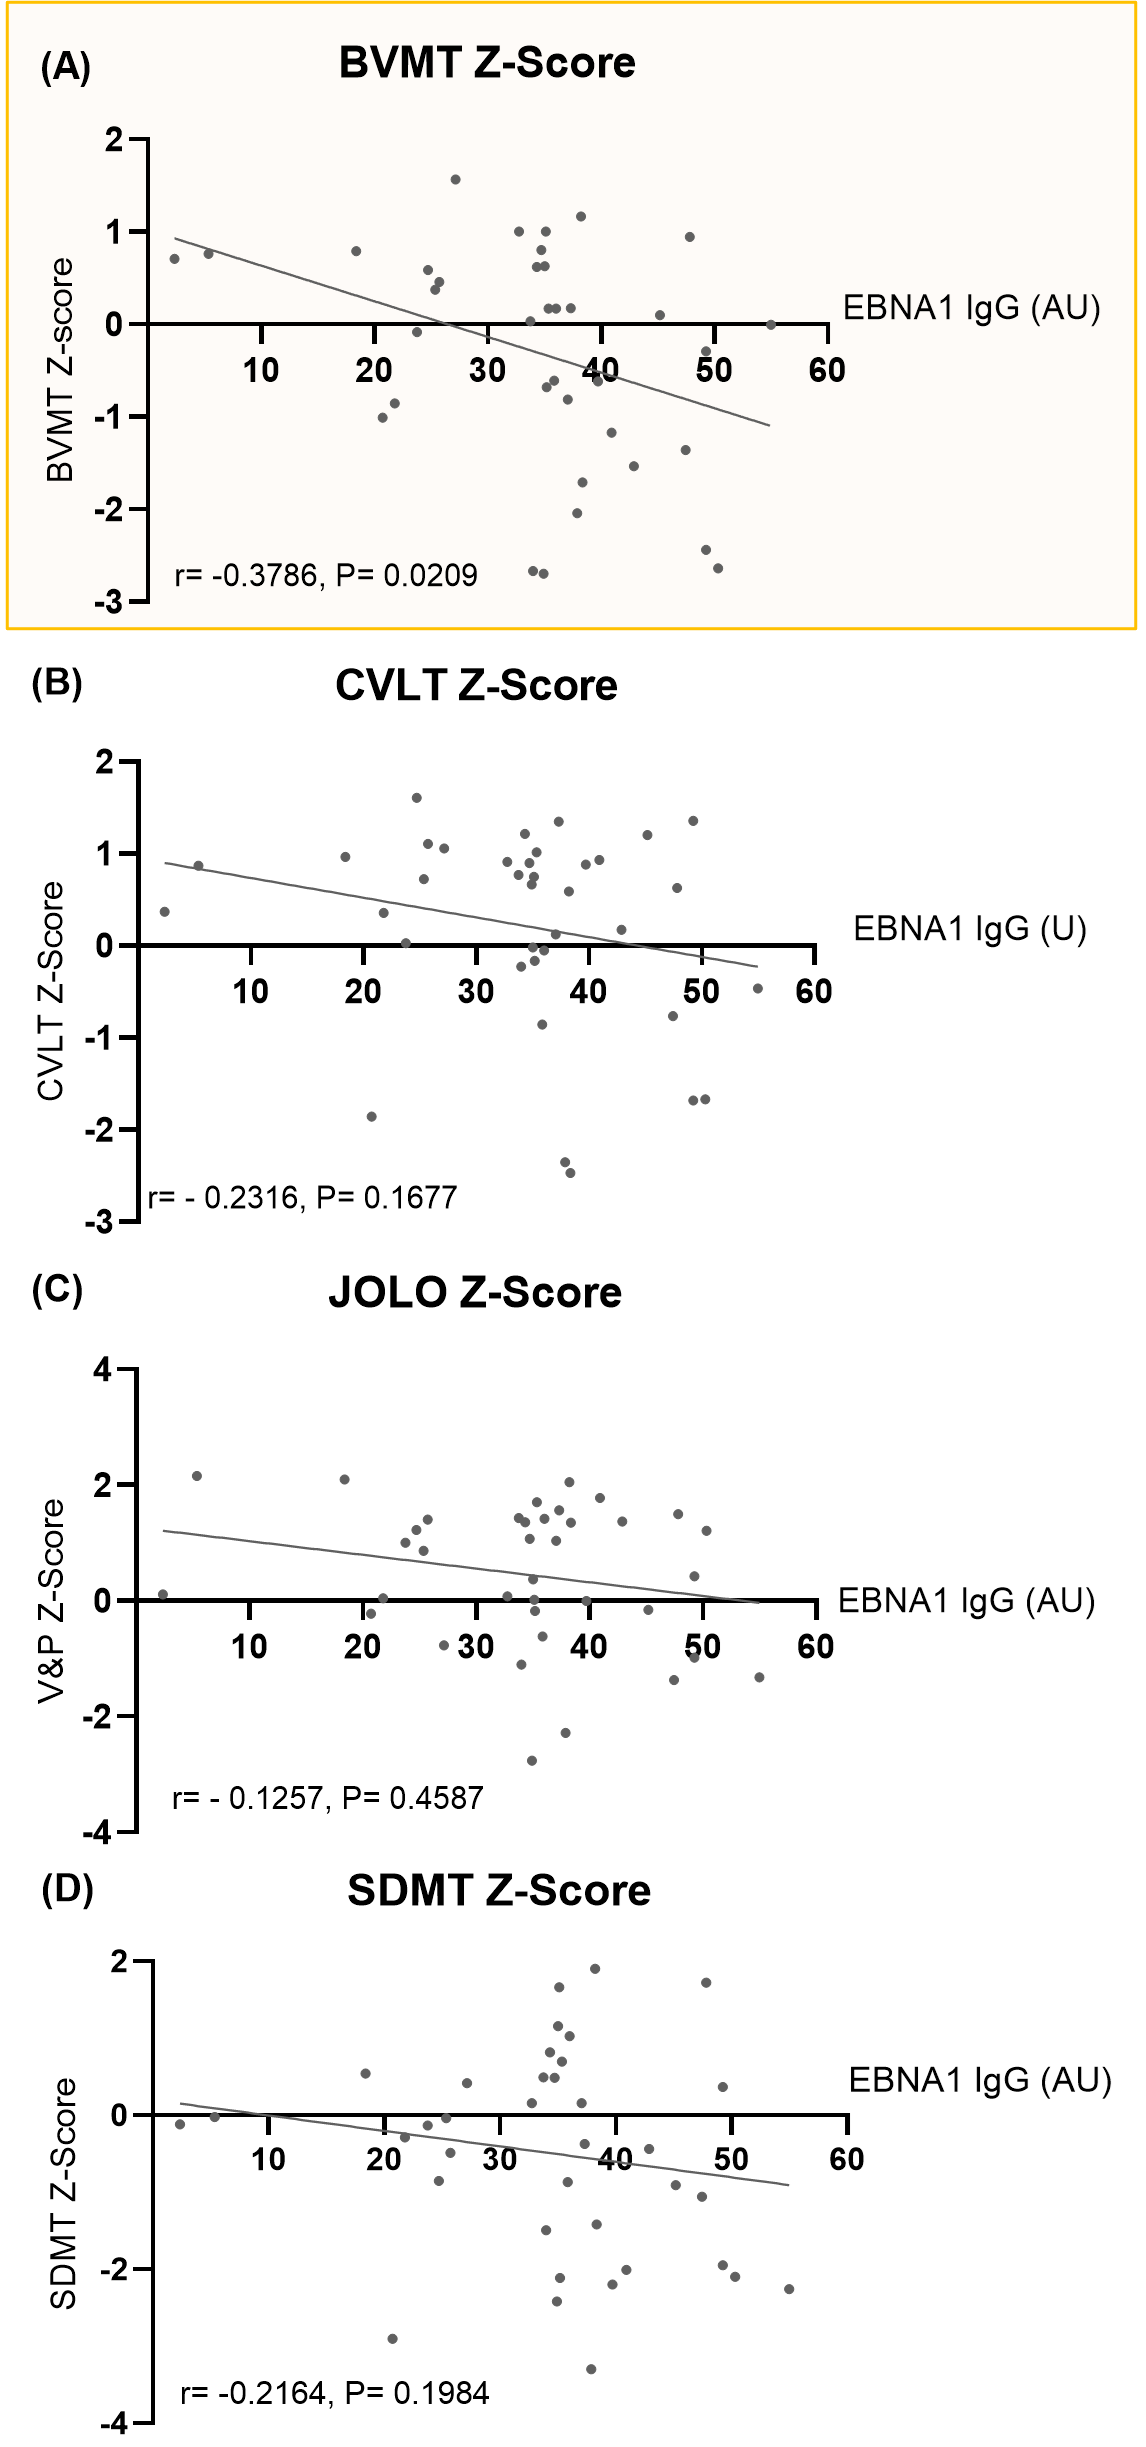

Association Between EBV Antibody Levels and Cognitive Function

Figure 4 1

Figure 3. Correlation of EBNA1 IgG Titers with Minimal Assessment of Cognitive Function in Multiple Sclerosis (MACFIMS) Scores. Scatter plots showing the correlation between EBNA1 IgG titers and Z-scores from (A) Brief Visuospatial Memory Test (BVMT), (B) California Verbal Learning Test (CVLT), (C) Judgment of Line Orientation (JOLO), and (D) Symbol Digit Modalities Test (SDMT). The correlation coefficient (r) and p-values (P) were assessed using Spearman rank correlation.

Figure 4 2

Figure 3. (E–H) Scatter plots showing the correlation between EBNA1 IgG titers and Z-scores from (E) Paced Auditory Serial Addition Test 2-second version (PASAT2), (F) PASAT 3-second version (PASAT3), (G) Delis-Kaplan Executive Function System - Color-Word Interference Test: Condition 3 (DKEFS CS), and (H) DKEFS - Design Fluency: Condition 1 (DKEFS DS). The correlations were assessed using Spearman rank correlation.